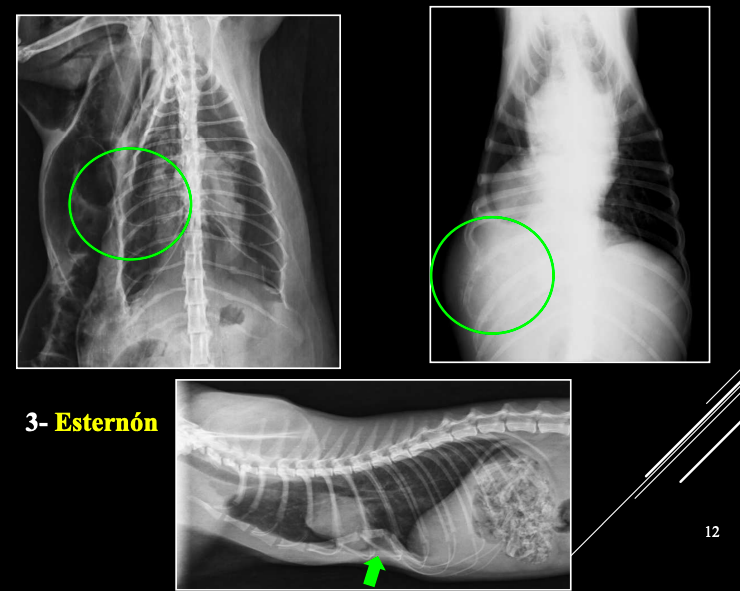

3. Esternón

- Escasas alteraciones significativas.

- Posibles: neoplasias, infección, pectus excavatum (Problemas aspiratorios, puede ser congenita) o pectus perinatum (poco frecuentes, perinatum aun menos)

- Alteraciones de posición del mediastino (Desplazamiento mediastino VD)

- Alteraciones en la visualización de estructuras mediastinicas (Neumomediastino LL)

- Alteraciones de la anchura del mediastino (Derrame mediastinico o masa mediastinica VD)

1. Desplazamientos

- Artefacto (rotación): desplazamiento no real. Si se ve el esternon está mal

- Por enfermedad pleural (neumotórax): desplazamiento no real.

- Masa mediastínica: desplazamiento real.